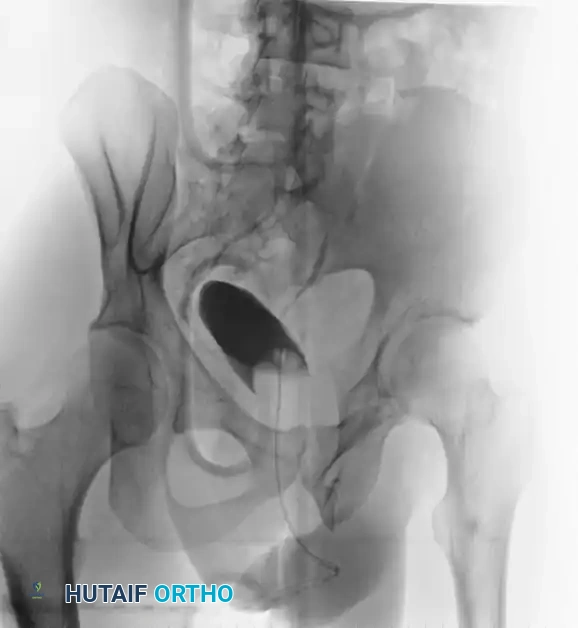

Preoperative Evaluation:

The preoperative AP, inlet, and outlet views demonstrate severe pubic diastasis, bilateral pubic rami fractures, and gross widening/displacement of the posterior SI joints.

FIGURE 56-45: Young and Burgess anteroposterior type III (AP III) pelvic ring injury with pubic diastasis and bilateral pubic rami fractures. A-C, Preoperative anteroposterior, inlet, and outlet views, respectively. D, Preoperative CT scan.